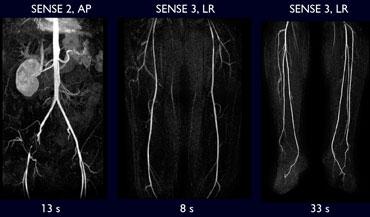

Lấp đầy không gian k theo kiểu trung tâm cho phép thu nhận phần tối ưu của không gian k trung tâm trong pha động mạch của quá trình ngấm thuốc tương phản từ trong một khoảng thời gian ngắn. Thời gian còn lại được sử dụng để tăng độ phân giải không gian. Hiện tượng ngấm thuốc tĩnh mạch sẽ không gây nhiều vấn đề vì khi các đường ngoại vi của không gian k được lấp đầy dữ liệu, điều này không đóng góp nhiều vào độ tương phản của ảnh.

Cửa sổ động-tĩnh mạch (AV) sẽ được mở rộng, cho phép thời gian chụp dài hơn. Nếu không có tùy chọn lấp đầy không gian k theo kiểu trung tâm, hãy sử dụng lấp đầy không gian k tuyến tính (xem mẹo và thủ thuật).

Không sử dụng cùng một vùng chụp cho mỗi vị trí, mà cần điều chỉnh kích thước và góc nghiêng của các vùng chụp ở mức chậu, đùi và cẳng chân. Đặc biệt ở mức đùi, một vùng chụp nhỏ thường là đủ. Điều này tiết kiệm thời gian và cho phép chuyển nhanh sang chụp cẳng chân.

Ở mức cẳng chân, đặc biệt khi cần bao gồm cung gan bàn chân, cần một vùng chụp lớn. Độ phân giải không gian ở mức này phải cao. Điều này dẫn đến nhiều lát cắt mỏng hơn và thời gian chụp dài hơn. Cách khắc phục hiện tượng ngấm thuốc tĩnh mạch ở cẳng chân khi thời gian chụp dài hơn sẽ được giải thích sau.

Ở bệnh nhân đau cách hồi, quy trình chụp một bước với hình ảnh 3 vùng tuần tự là tối ưu.

Ở bệnh nhân thiếu máu cục bộ giai đoạn nặng, trước tiên khảo sát cẳng chân bao gồm cả cung gan bàn chân. Tiếp theo, cần tiêm thuốc tương phản từ riêng biệt để khảo sát vùng Động mạch Chủ-Chậu và Đùi. Tùy thuộc vào tốc độ của hệ thống MRI, thuốc tương phản từ có thể được tiêm với tốc độ cao hơn.